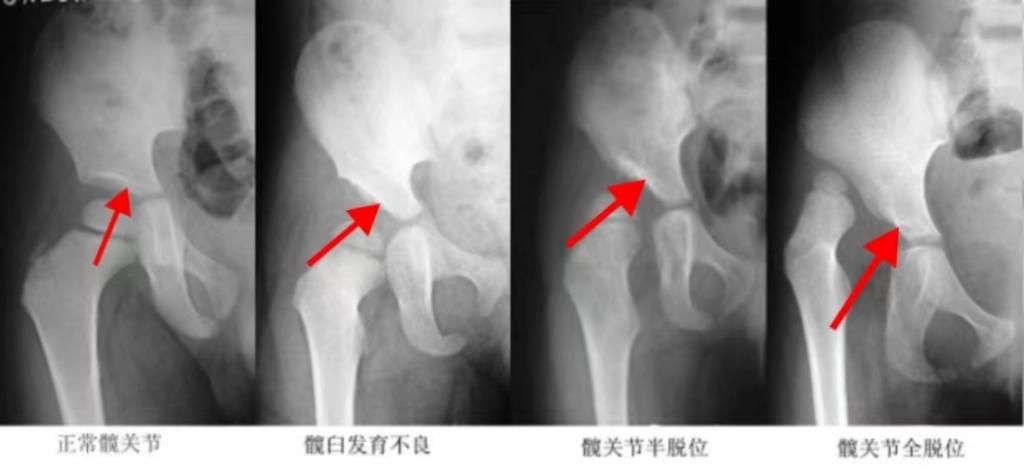

一、什么是發(fā)育性髖關(guān)節(jié)發(fā)育不良(DHH)

發(fā)育性髖關(guān)節(jié)發(fā)育不良(DDH)既往被稱為先天性髖關(guān)節(jié)脫位(CDH), 是小兒比較常見的先天性畸形之一,該病呈現(xiàn)一種動態(tài)的發(fā)育異常。

附圖一